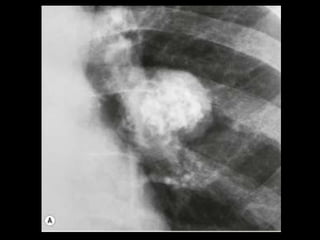

Malformação arteriovenosa(MAV)

TC: o aspecto típico é de uma massa regular,

lobulada, redonda ou oval, ou até o de uma

formação serpenginosa, com menos de 1 cm a

vários cm de tamanho, associada a uma artéria

nutriz visivelmente aumentada e uma veia de

drenagem alargada;

Uma ANGIO-TC geralmente faz o diagnóstico;

Tratamento pode ser realizado com terapia

embólica.

MAV complexa

Malformação arteriovenosa(MAV) TC:o aspecto típico é de uma massa regular, lobulada, redonda ou oval, ou até o de uma formação serpenginosa, com menos de 1 cm a vários cm de tamanho, associada a uma artéria nutriz visivelmente aumentada e uma veia de drenagem alargada; Uma ANGIO-TC geralmente faz o diagnóstico; Tratamento pode ser realizado com terapia embólica.